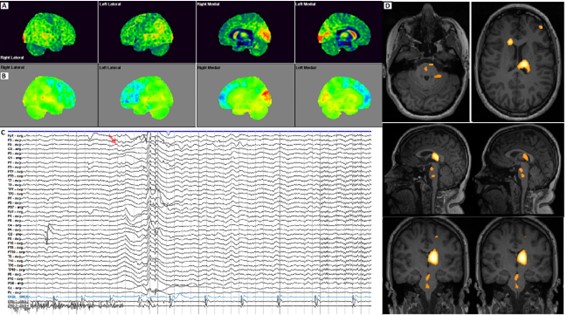

Figure 1

(Fig. 1) 18F-FDG PET/CT (A, PET cortical surface normalized; B, PET cortical Surface parametrical maps) both bilateral left predominant decreased radiotracer uptake in medial and lateral association frontal cortex. EEG (C, representative EEG epoch illustrating the onset of a typical atonic seizure in this patient. The record is displayed over 10 seconds/page in a referential montage with a common-average reference (International 10–20 system), and supplementary frontotemporal electrodes. High-and low-frequency filter settings were 30 Hz and 1 Hz, respectively. EMG leads (bottom two channels) were placed over both deltoids to capture muscle activity. The red arrow indicates the moment of seizure onset, characterized by a generalized electro decrement accompanied by a high-voltage delta slow wave over the right hemisphere, followed by generalized delta activity most prominent in the frontotemporal regions. Superimposed on this slow activity, a low-voltage, fast (beta) rhythm emerges toward the end of the page. Notably, from the onset of the seizure, EMG activity markedly diminishes, consistent with the sudden loss of muscle tone characteristic of an atonic seizure. Ictal SPECT injection was performed in this atonic seizure, 4 seconds after the onset in a seizure of 15 seconds. SISCOM images using Neurocloud® Software using AAL Atlas age-matched normal controls (D, Z-scores superimposed on MRI) revealed a markedly high uptake in left thalamus (medial region), right head caudate nucleus, and mild to moderate in left middle frontal gyrus, left superior temporal gyrus (Table 1), and additionally in brainstem areas related to ascending reticular activating system (ARAS - interpeduncular nucleus, nucleus reticularis pontis caudalis with anterior and left extension).